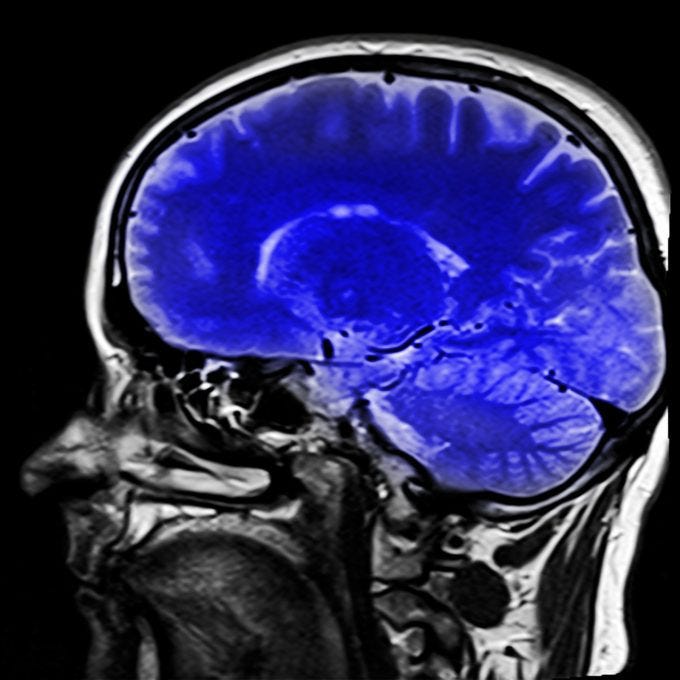

Emozioni cervello amigdala. Lopinione corrente e che alcune strutture cerebrali siano particolarmente importanti per lesperienza e lespressione dellemozione. Httpsbitly2vitqvh lamigdala deve il suo nome alla sua forma. Lamigdala o corpo amigdaloideo e un complesso nucleare situato nella parte dorsomediale del lobo temporale del cervello che gestisce le emozioni e in particolar modo la paura.

E una parte del cervello lorgano piu importante del sistema nervoso centrale posizionata tra le tempie. Lamigdala governa le emozioni basiche ed e responsabile della memoria dei nostri traumi. Ci hanno insegnato che lamigdala e specifica per la paura.

Come abbiamo gia osservato non ce alcuna distinzione tra stimolazione reale esterna e immaginata interna nellevocare emozioni e segnali efferenti. A livello anatomico scientifico viene definita anche come un gruppo di strutture interconnesse di sostanza grigia facente parte del sistema limbico posto sopra il tronco cerebrale nella regione rostromediale del. A lei si devono emozioni come rabbia paura ed e essenziale per listinto di sopravvivenza.

Lamigdala attribuisce significato emotivo a informazioni di stimoli provenienti dal mondo esterno dallinterno del corpo e dal cervello come pensieri e ricordi. E molto piccola ma estremamente importante. Lamigdala fa parte del cosiddetto encefalo umano la parte profonda in cui prevalgono le emozioni basiche come la rabbia la paura e listinto di sopravvivenza essenziale senza dubbio per la sopravvivenza di tutte le specie.